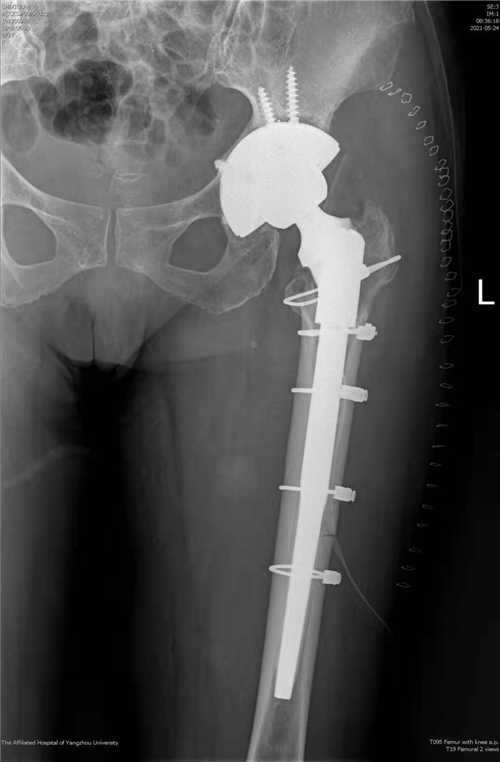

近日,我院骨科关节组副主任医师徐松诊疗团队成功为一名髋关节假体松动患者实施了全髋关节翻修手术。该手术为我院首次独立完成,打破了我院髋关节翻修需请上级专家会诊或转上级医院手术的传统,填补了我院关节技术的空白,为扬州地区髋关节假体松动患者的治疗提供了便利、减轻了经济负担,为该类患者带来了福音。

据了解,患者73岁,女性,7年前因创伤性股骨头坏死接受左全髋关节置换手术治疗,术后髋关节活动一切如常,近3年来患髋逐渐出现疼痛、活动受限,患者渐渐不能行走,长期卧床。因手术难度大、风险高,患者辗转扬州多家医院均遭拒,或建议其上级医院就诊。患者来到我院骨科,接受左全髋关节翻修手术,术后第四天即可下地正常活动,恢复后的患者激动地说:“躺了2年多,我终于可以自己站起来了!”

骨科副主任医师徐饶介绍,人工髋关节置换是我院常规开展的一种手术,但人工假体有使用寿命,经长期不规范使用后假体会出现松动,进而进一步影响髋关节功能,情况严重的患者只能长期卧床,患者生活质量受到严重影响,因此需要再次对人工髋关节进行翻新修复,以恢复髋关节的功能。因为人工髋关节的功能是建立在人工假体的稳定性及周围软组织平衡性基础之上,所以对局部骨量及软组织质量要求都比较高,然而松动的假体往往会破坏局部正常的骨结构,引起局部骨量流失,加之初次手术造成的大量骨质缺失、疤痕粘连、软组织解剖结构异常,该类手术难度往往非常大。现在,经过多年技术的积累与沉淀,我院骨科关节组已经完全具备了独立开展此类手术的技术条件,造福了更多扬州百姓。